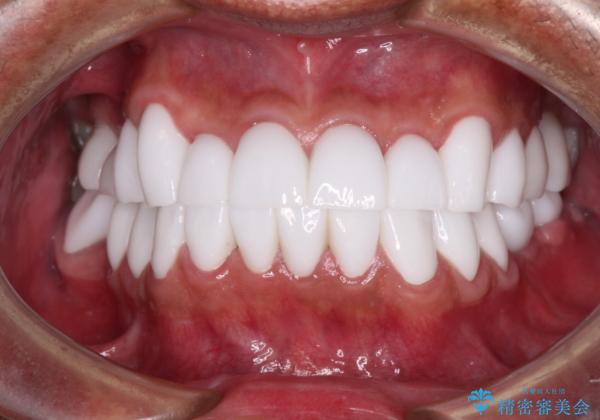

不自然なくらい真っ白にしたいとのことでしたので、透明感のないフルジルコニアクラウンを用いて補綴することとしました。

本来、あまりにも不自然な歯となるため、フルジルコニアクラウンを前歯に使用することは、咬合力が強すぎる場合を除き、ほとんどありません。

それでも、色調、形態ともに不自然なくらい真っ白な歯をご希望でしたので、患者様には大変満足していただきました。